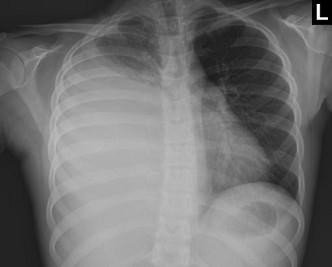

下列图像最佳诊断是什么 ( )A、肺癌B、肺结核C、气胸D、肺不张E、脓胸

选项 A、肺癌 B、肺结核 C、气胸 D、肺不张 E、脓胸

答案 E